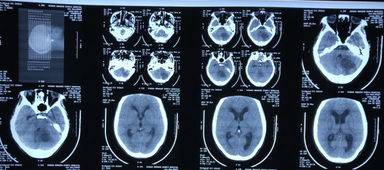

3、脑部电脑断层扫描:

通过这种方法进行检查后 , 能够观察到胸腺部位的肿瘤 , 并且能够清楚的观察 , 肿瘤的性状等 , 其重症肌无力患者年龄大多为40岁以上 。